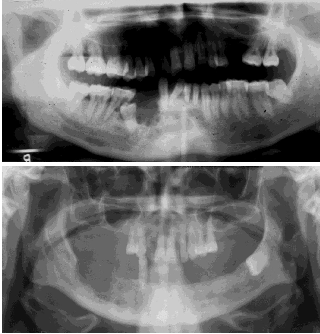

What’s an ameloblastoma?

May mimic other radiolucencies.

What’s a unicystic ameloblastoma?

Account for ~15% of Ameloblastoma. Equal distribution between maxilla and mandible. Usually unilocular associated with the crown of an un erupted tooth peak age 35 years.